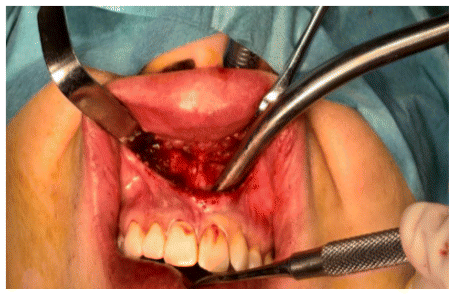

The surgical procedure was performed following minimally invasive orthognathic surgery, involving a mucoperiosteal incision in the anterior vestibular region of the maxilla. The surgical access measured approximately 2 cm, extending from one central incisor to the other. (Figure 4)

A subperiosteal dissection was performed in the nasomaxillary region, followed by the creation of a myomucosal tunnel in the posterior area of the maxilla to facilitate the passage of the implant. (Figure 5)